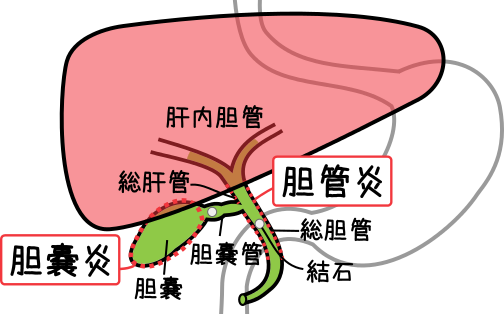

胆嚢は一部分肝臓にくっついてしっかり固定されている場所があり、そこを針で狙うと体の表面から比較的安全に針先が胆嚢まで到達させることができるのです。 なお、『』で解説した閉塞性と急性胆嚢炎は、 どちらも緊急に処置が必要な疾患です。 多くは右肩や右背部に痛みが放散します。

疾患での役割 [ ] 胆石症 [ ] 最大25%の人間が、、、およびで構成されたを持つ。 急性胆のう炎では、胆のうが浮腫などにより肥大しますが、慢性胆のう炎では胆のう壁が分厚くなり、胆のう自体のサイズは萎縮していきます。 写らない場合でも、胆嚢を映し出す造影剤があって、それを経口的、あるいは経静脈的に与えることにより胆嚢を映したり、内視鏡的逆行性胆管造影法によって、中にある石をみつけます。